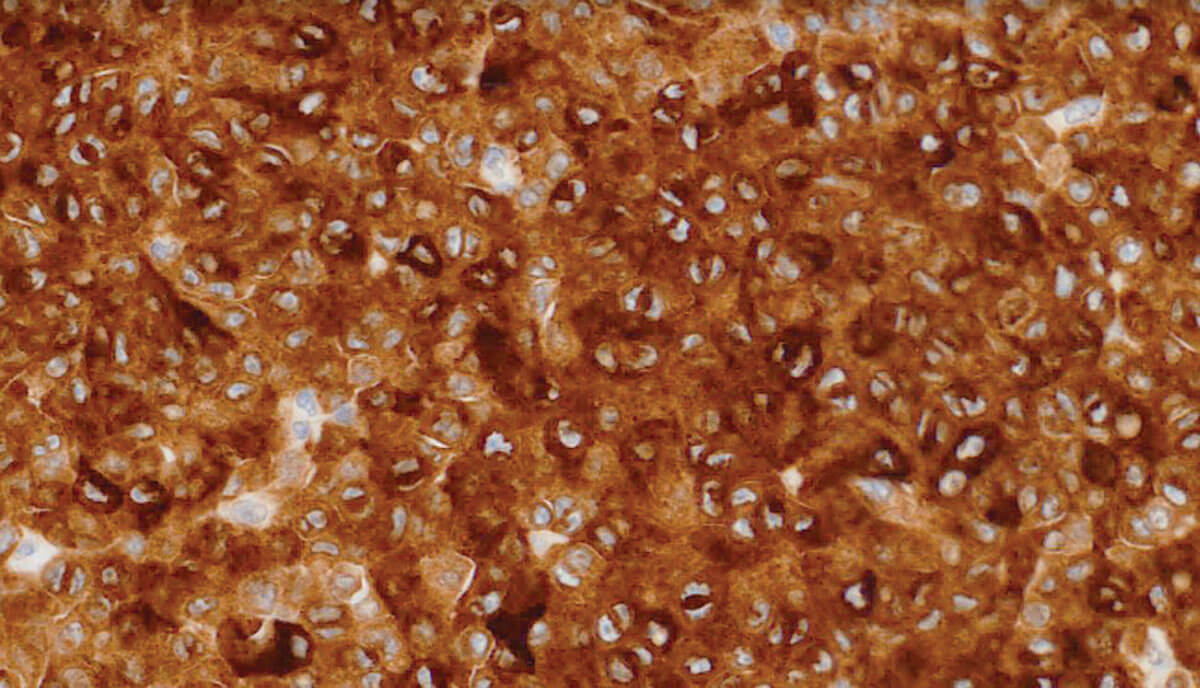

Figure 2b: MelanA x20.

Figure 2 shows a representative H+E and a melanA immunohistochemical stained section of the lesion.

- Figures 1 and 2 demonstrate a large, nodular partially pigmented invasive melanoma of the inferior bulbar conjunctiva. The melanoma cells were predominantly of epithelioid cell type and were strongly immunopositive for melanA. There was a mild, patchy infiltration of tumour infiltrating lymphocytes and melanophages. Other features present but not shown here, include: overlying conjunctival melanoma in situ; perineural invasion; and involvement of the trabecular meshwork by melanoma cells. The melanoma was 1.5mm from the deep cutaneous surgical margin of the lower lid. All other surgical margins were clear. The inferior forniceal and palpebral conjunctiva were clear. Likewise, the lower eyelid skin, upper eyelid skin and conjunctiva, lacrimal gland, nasolacrimal system and optic nerve were all clear of in situ and invasive melanoma. There was no BRAF V600E mutation present.